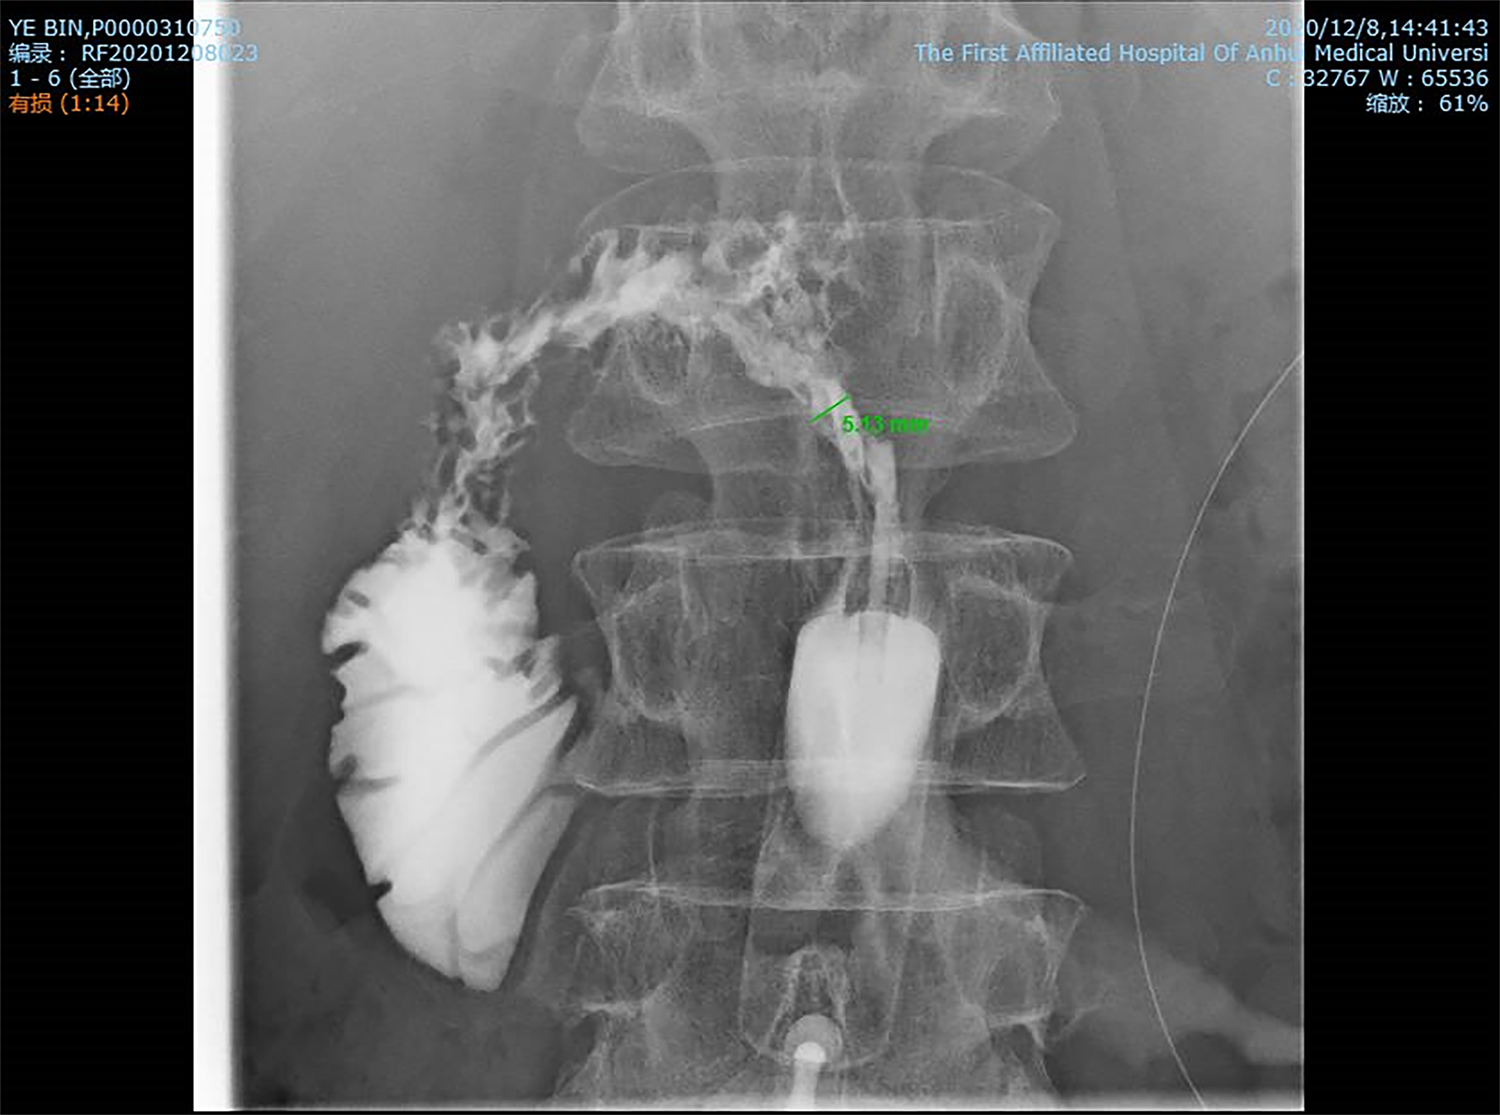

这位王先生系胃癌术后,重度营养不良,切口出现反复溃烂,肉眼可见浑浊液体流出并伴有腹痛,到我院高新院区胃肠外科二病区求诊,曹先东主任详细地询问了王先生的病史,给患者行造影检查,发现造影剂从瘘口直通十二指肠,确诊为“十二指肠残端瘘”,加之高位肠瘘导致消化液腐蚀腹腔,患者生命垂危。经过和患者及其家属进行有效沟通后,都一致要求在我院胃肠外科二病区实施腹腔开放术为主的综合治疗。在科主任常家聪教授、曹先东教授指导下,胃肠外科二病区肠瘘与腹腔感染治疗团队成员汤亲青博士、周波博士、吴伙博士及芮红霞护士长带领的护理团队迅速为患者制定治疗方案:双套管持续冲洗引流、腹腔开放、全肠内营养支持。经过术前精心准备,术中细致操作,患者腹腔感染得到有效控制,窦道形成良好,经窦道造影评估时机成熟后,应用生物胶封堵肠瘘。经过两个月的治疗和悉心护理后,患者饮食排便正常,肠瘘闭合,顺利痊愈出院。